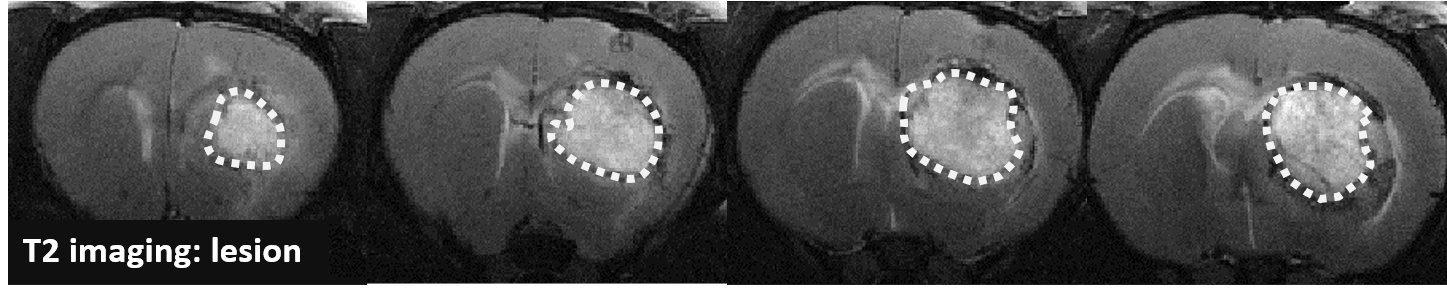

Changes in the volume of both the lesion (T2) and the haematoma (T2*) can be located, measured and tracked with MRI brain imaging. (Illustration: Figure 1: rat on day 1 , Figure 2: mouse on day 1).

Long term monitoring enables researchers to highlight the impact of a treatment over the longer term and to observe the animal’s functional recovery phase (Figure 3). It also makes it possible to track the reduction in post-induction oedema and tissue remodelling in the damaged area. The activation of those processes results in a reduction in the size of the lesion (phagocytosis of cellular debris, glial colonisation, etc.).